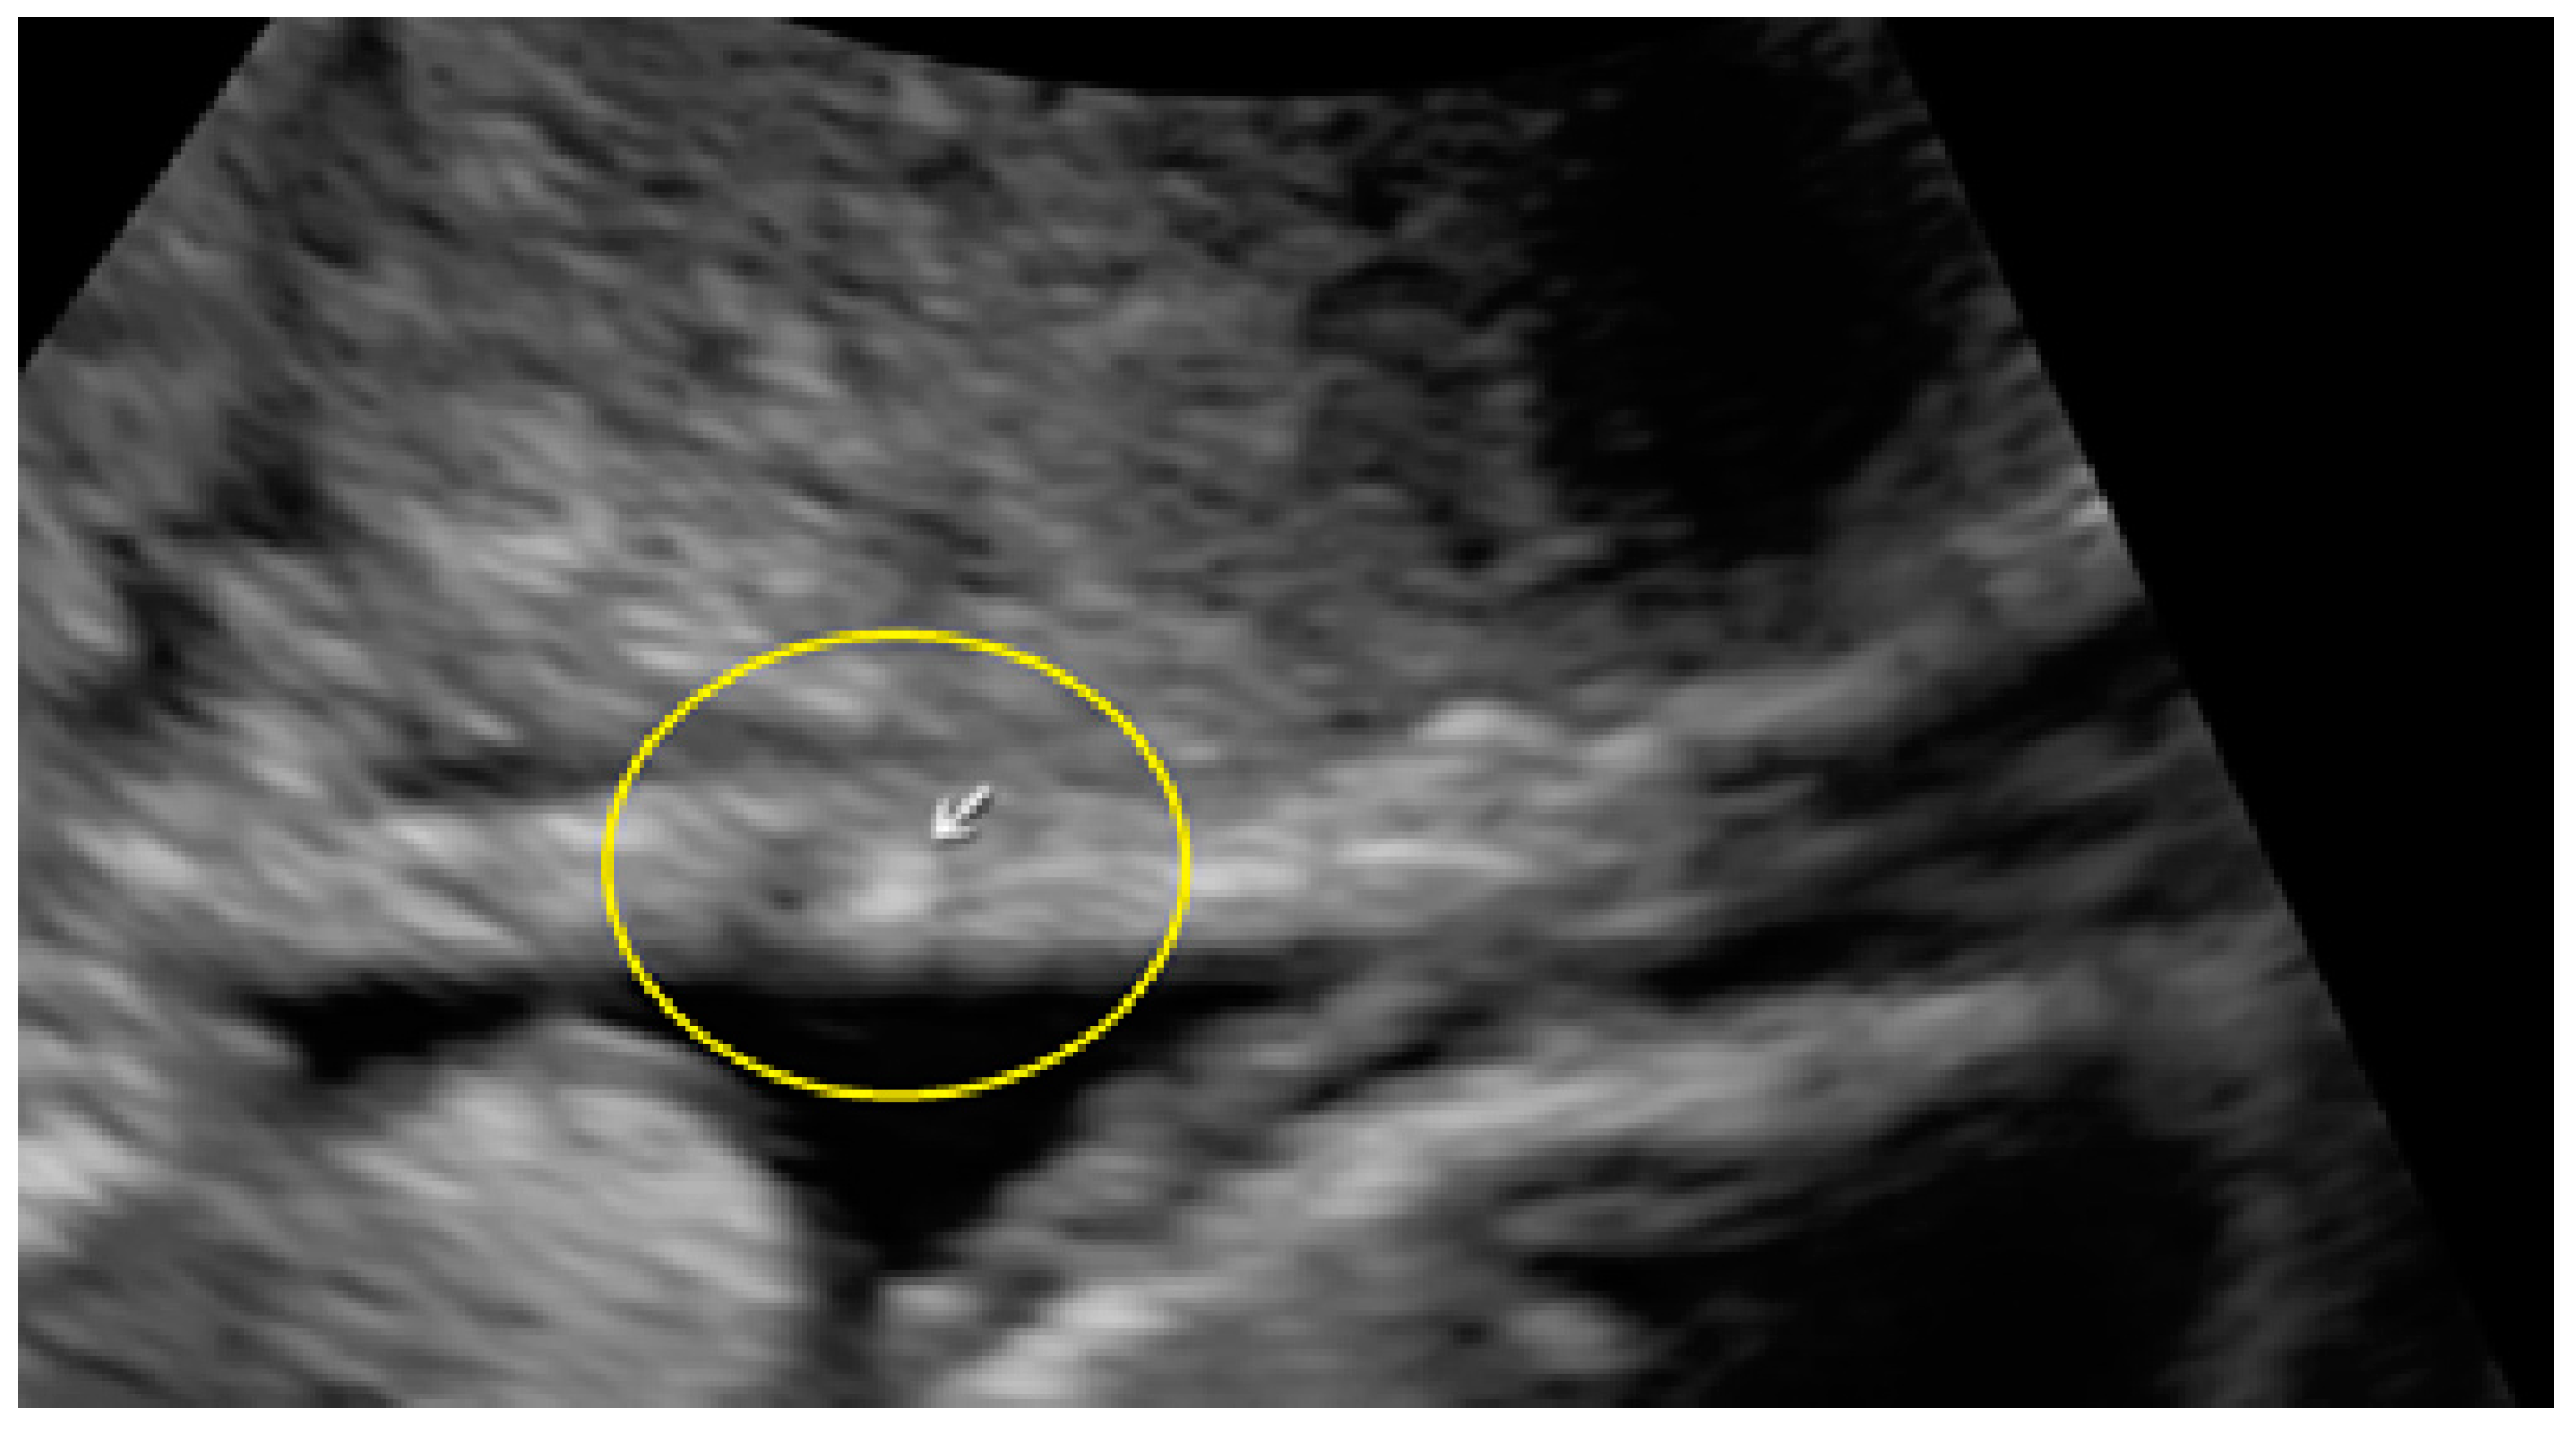

- The presence of hyperechoic foci (we called this a “pearl”).